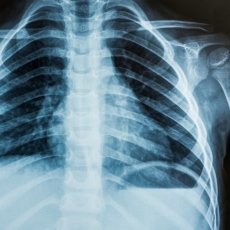

X-rays are a type of radiation called electromagnetic waves. X-ray imaging creates pictures of the inside of your body. The images show the parts of your body in different shades of black and white. This is because different tissues absorb different amounts of radiation. Calcium in bones absorbs x-rays the most, so bones look white. Fat and other soft tissues absorb less and look gray. Air absorbs the least, so lungs look black.

The most familiar use of x-rays is checking for fractures (broken bones), but x-rays are also used in other ways. For example, chest x-rays can spot pneumonia. Mammograms use x-rays to look for breast cancer.